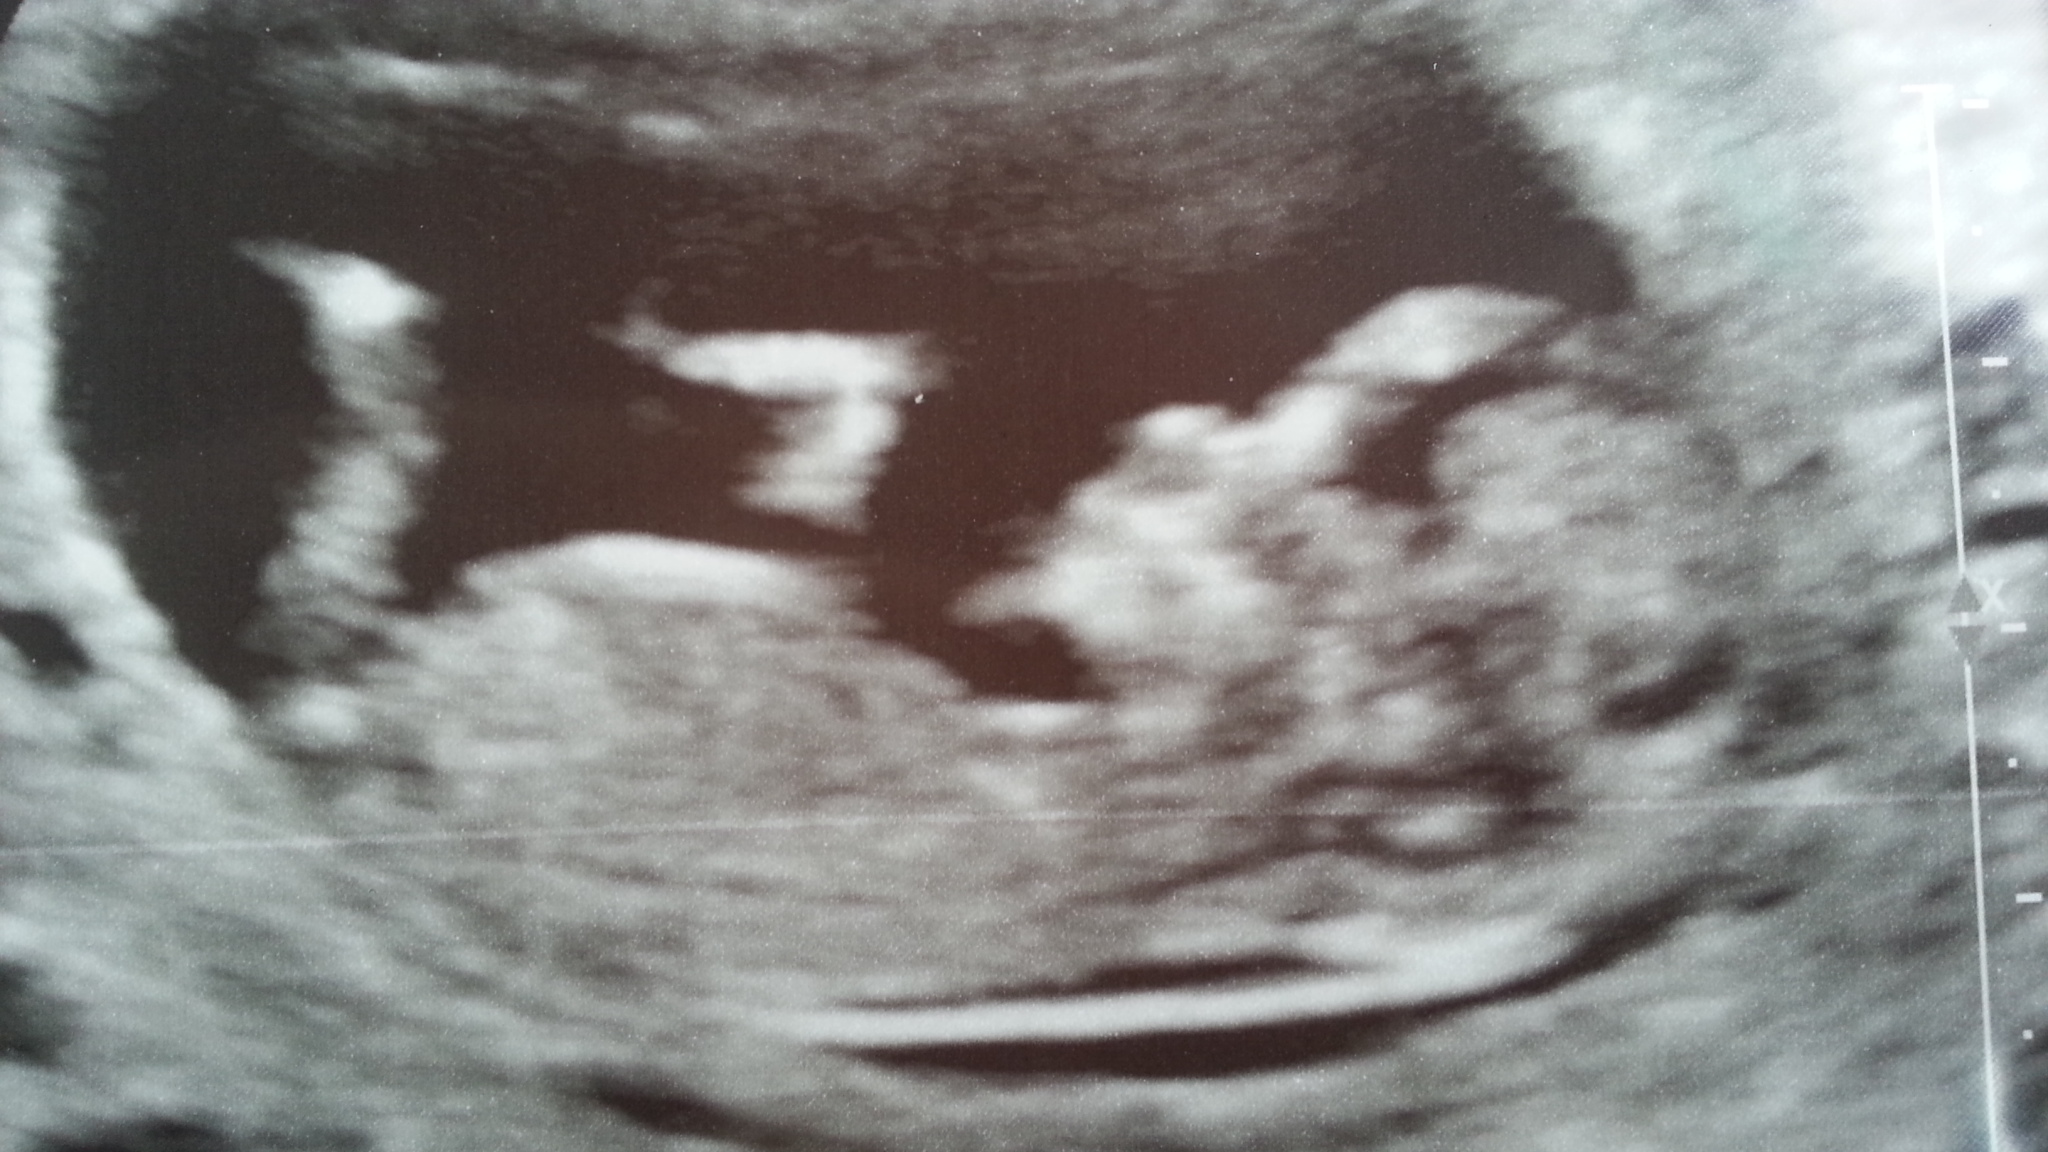

12+2wks baby being ridiculously uncooperative :-( not even sure I can make out a nub :-(

Any guesses greatly appreciated. Please be honest.

For some reason I'm really feeling boy.